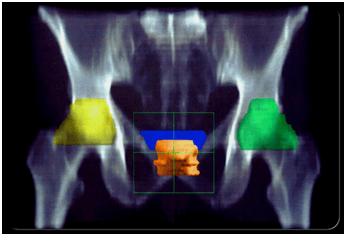

MRI SCAN/PET SCANS will help diagnose the stage of disease.

Stage 1 and Stage 2 and selected cases of stage 3 diseases are treated with equal success by Radiation Therapy ,surgical excision or a combination of the two in selected

Radiation Therapy for Prostate cancer:

Usually for patients unfit for surgery or choosing this option. the results are comparable to surgery . Although rectal side effects like bloody and mucus diarrhea , erectile dysfunction and harmonal imbalances are reported.